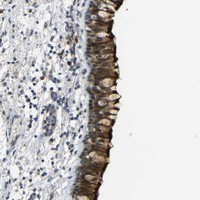

- Immunohistochemical staining of human bronchus with C16orf89 polyclonal antibody (Cat # PAB20664) shows strong nuclear and cytoplasmic and membranous positivity in respiratory epithelial cells at 1:50-1:200 dilution.

- Immunohistochemistry (Formalin/PFA-fixed paraffin-embedded sections)